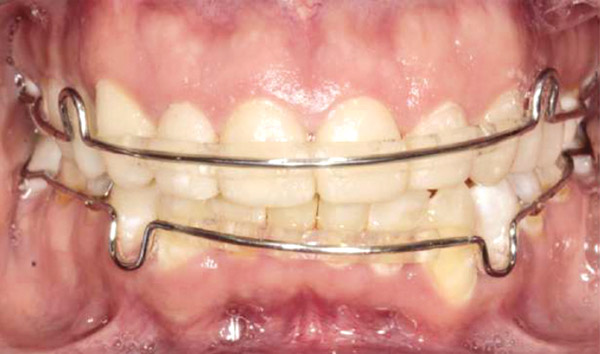

Se realizó una expansión dentoalveolar superior mediante un expansor con tornillo de 3 vías con efecto sagital y transversal, (Figura 9), preparación de la superficie dental para el bondeo de brackets por medio del arenado con partícula de sílice 60 μm a 40 lbs de presión con una angulación de 45° por un tiempo 3 a 4 segundos por diente, (Figura 10 y 11), y una fase ortodóncica con brackets prescripción Roth 0.022 x 0.028, tubos bondeables en 6's y 7's. Para la corrección del apiñamiento con alineación y nivelación utilizando una secuencia de arcos NiTi 0.014, 0.016 0.020 superior e inferior, NiTi 0.017 x 0.25 acero 0.018, 0.020 superior e inferior y stripping antero inferior. Para obtener la clase II molar y canina bilateral con mecánica de elásticos dobles bilaterales clase II largos con elásticos 1/8 6 ½ oz y stripping postero superior, para la corrección de la línea media con el uso de elásticos de línea media de 3/16 6 ½oz. La obtención del adecuado overjet y overbite se logró mediante el stripping, las cadenas intramaxilares y elásticos intermaxilares. Se obtuvo la máxima intercuspidación, paralelismo radicular y oclusión funcional en la fase de detallado mediante arcos de acero 0.017 x 0.025 y 0.019 x 0.025 superior e inferior, con dobleces de primer, segundo y tercer orden; restauración protésica en los dientes con fluorosis se trabajó mediante el tallado, la toma de impresiones, (Figura 10 y 11) y la colocación de la resina termocurada.

Figura 9. Aparato expansor.